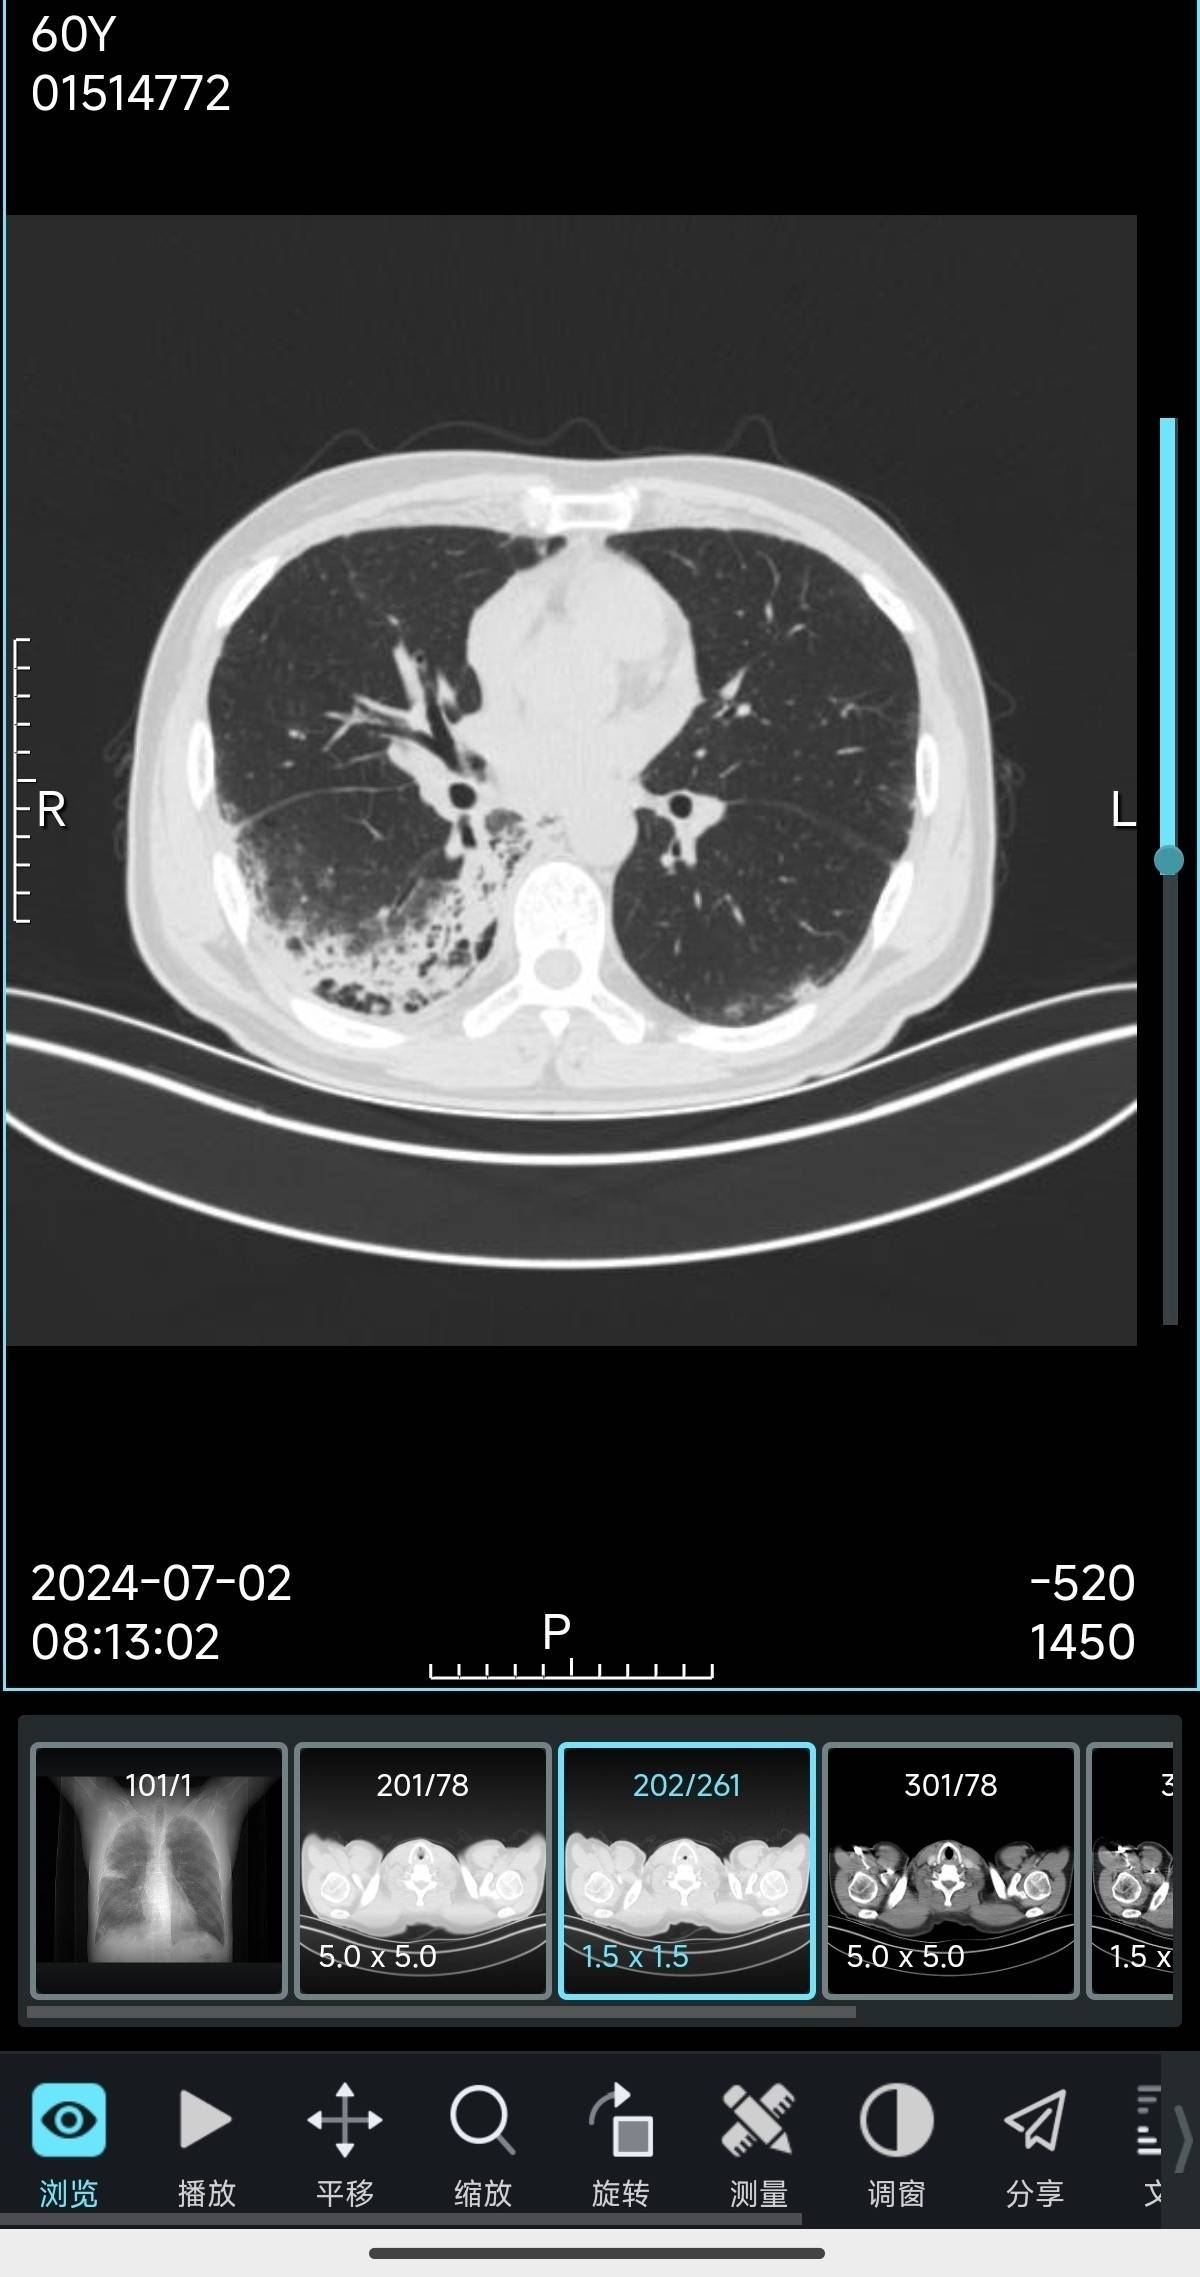

今天结果都出来了,腹盆ct跟之前一样,没有什么问题,但是胸部增强ct的结果跟之前有了变化,原来右肺下叶的实性结节被多发斑片状浸润影掩盖了,右肺门及纵隔多发肿大淋巴结,部分较前稍大,这个情况个人估计是比之前变差了。

我自己也在学着看ct影像,这次的图像确实跟之前的几次明显不一样,以前是一块比较明显的灰色,现在变成了一大片比较浅的灰色,应该是肿瘤开始侵犯其他部位,变差了的意思吧。